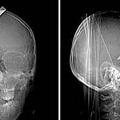

Sreča v nesreči Neverjetno preživetje vboda z nožem Rentgenski posnetki glave najstnika, na katerih je viden globok vbod v glavo, kažejo, da je lahko resnično srečen, da j…